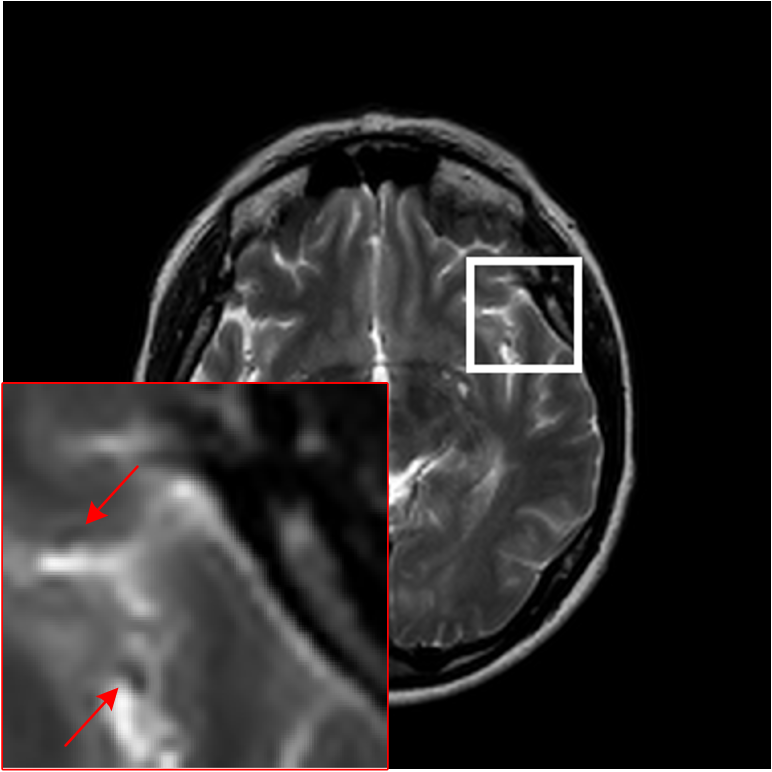

Figure 10: The reconstruction results on complex-valued MRI data. (a)-(c) are the PSNR values of different methods with three sampling masks and five sampling rates, in which the x-axis represents sampling rates. (d) is the standard deviation of PSNR values on different methods when using 30% sampling rates, in which the x-axis represents sampling masks. And (e)-(j) are the errors of six CSMRI methods.

We evaluate the performance of the proposed model using PSNR on complex-valued data and compare with two optimization-based methods and three deep-learning methods. We present the PSNR results for all sampling masks and five rates in Figs. 10(a)-(c) and it is obvious that the proposed model outperforms other five methods, which can demonstrate the effectiveness of MDN model on complex-valued data. Additionally, we provide the standard deviation on 80 test images of different methods when using 30% sampling rates of three masks in Fig. 10(d). We can observe that deep-learning methods obtain more stable performance than DLMRI and Sparse MRI. In Figs. 10(e)-(j), we show the absolute value of residuals of different algorithms using 30% radial sampling rate. We can see that the proposed model has less noise-like errors than other five methods.